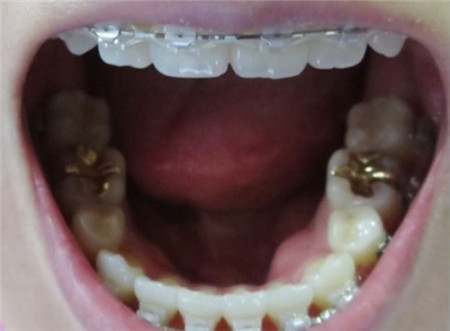

用弹簧装置牙齿移动空间,让内缩的牙齿被拉出来。

首先用弹簧装置牙齿移动空间后,将进行拔牙!偶尔会有人问我拔牙的相关事情,由于是否拔牙是因人而异的,因此进行精密检查后,如果牙齿移动空间足够的话,就没有必要拔牙。

像我是空间不足因此拔了牙!拔牙时候打的麻醉针药效退去之后很疼

矫正15~23个月后,开缝的上排牙齿根部变化。

矫正开始后每个月都要去一次牙科进行月诊,3个月的功夫虎牙就变得整齐了,其他牙齿也开始移动,牙齿间的空隙慢慢闭合。这时候牙根没有闭合, 随着每次月诊时会重新调换并加紧弓丝的同时,牙根间的缝隙也很快就闭合了!之后就要使用橡皮筋。